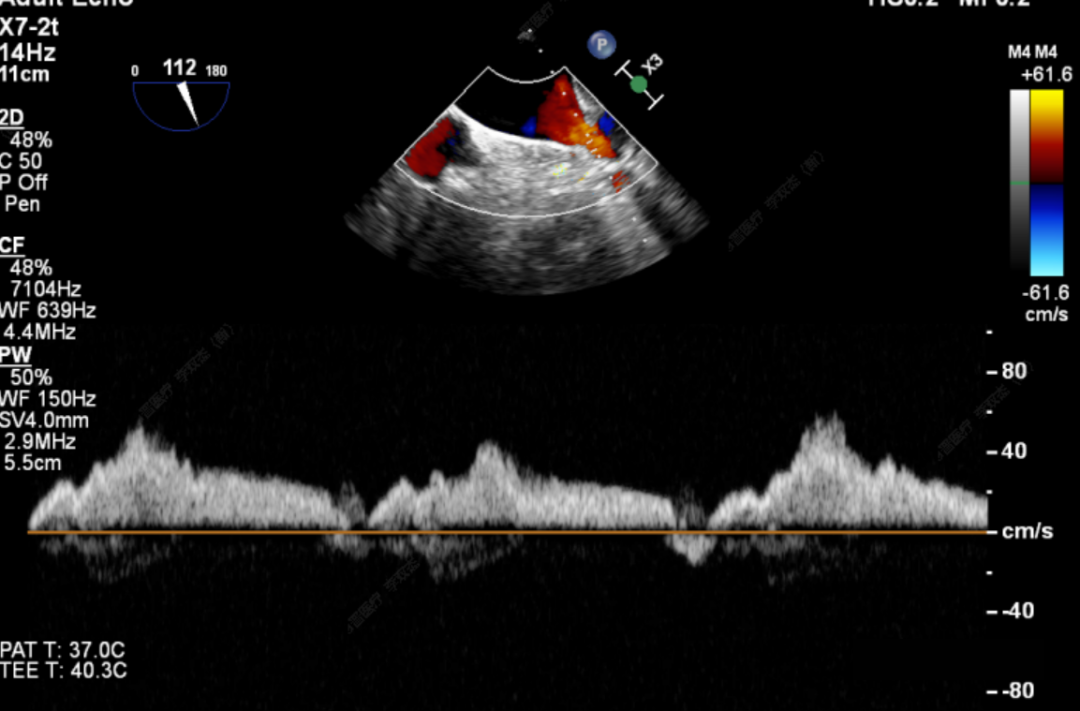

此次手术患者均为高龄、且外科高危的器质性二尖瓣反流,反流病变区域遍及前后瓣叶(一区、二区、三区),复杂及多样性的病变状况大大增加了手术的操作难度性,是对术者与器械稳定及有效性的巨大考验。术中,器械经股静脉穿刺房间隔,通过输送系统送入患者左心房,到达二尖瓣膜反流处,在经食道超声及DSA引导下,通过反复评估脱垂范围、抓捕位置、反流程度,确保细致操作、精准夹合、释放。术后即刻,患者反流显著减小,左房压下降,血流动力学改善明显,短暂过渡后,首位患者安返病房。导管室内,华西心脏瓣膜团队仍严阵以待,为之后两例手术做准备,经过团队之间紧密配合,三台手术均顺利完成。